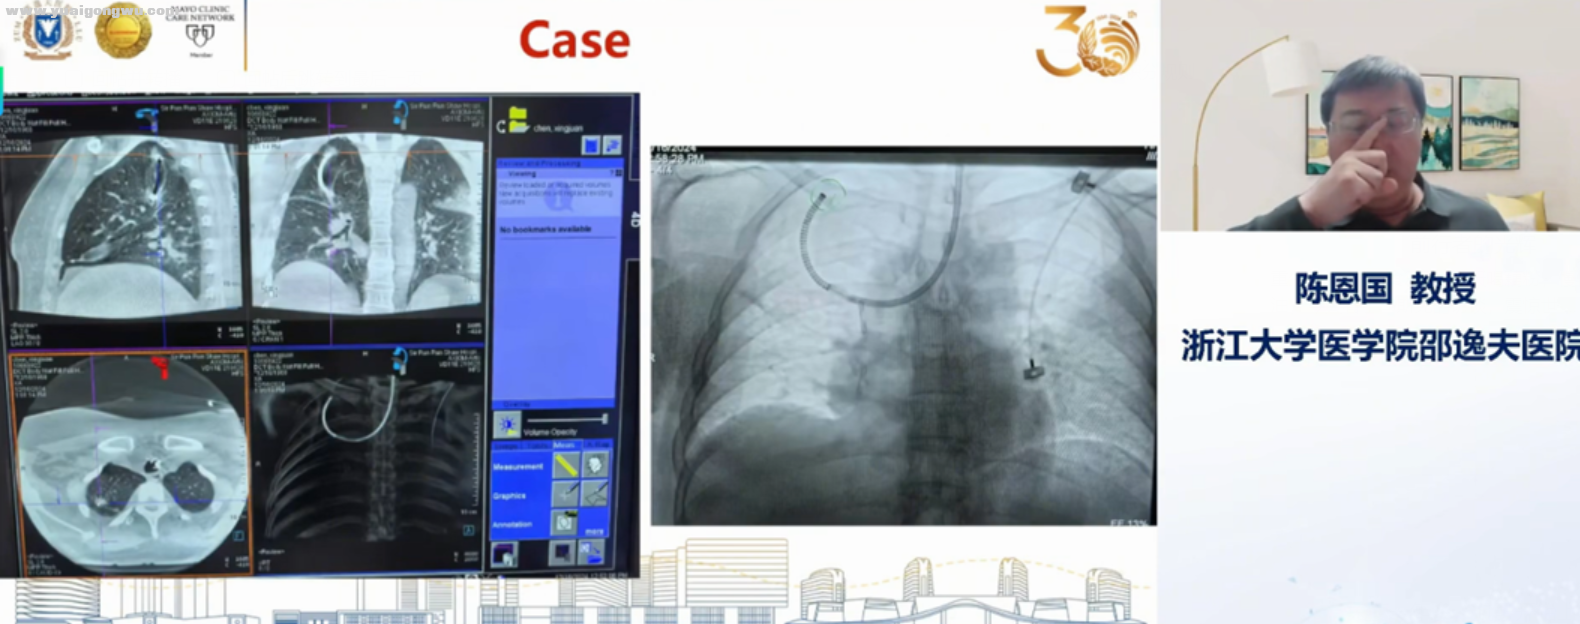

# F9 I& N' J0 H4 z& i提示信息,仅供参考。邵逸夫医院有机器人气管镜,全国第3家医院引进的,号称肺内活检无死角

图片信息仅供参考

机器人气管镜1.png

机器人气管镜2.png

安全高效

机器人气管镜3.png